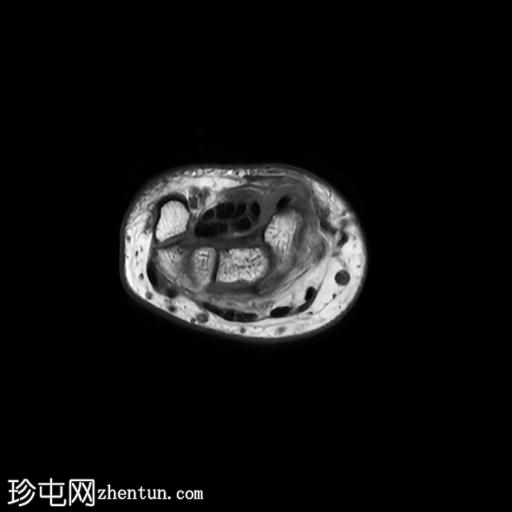

轴位PD序列

脂肪抑制序列

轴位

T1加权像

桡侧腕屈肌腱鞘内可见液体信号,提示腱鞘炎

手部桡侧腕屈肌腱远端扁平,邻近的大多角骨嵴和舟骨结节可见反应性骨髓水肿